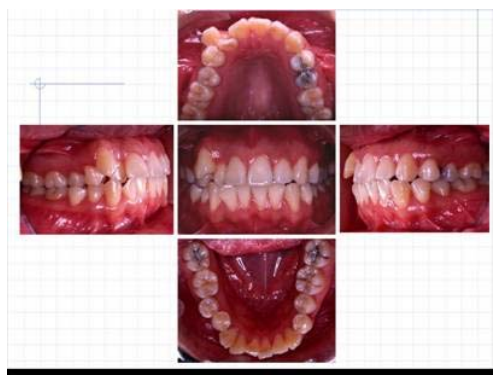

7. 患者為22歲女孩,口內照片如下圖,測顱分析中SNA 82度,SNB 80度,SN-MP 25度,上門牙角 度(SN-upper incisor axis)110度,下門牙角度(LI-MP)100度。有關診斷之思考中,下列何者 錯誤?

(A)上下顎骨關係正常 (B)上門牙角度正常,下門牙角度略外斜(proclined) (C)右側方咬合為安格氏二級咬合,左側方咬合為安格氏一級咬合 (D)顏面開展度過大(facial divergence)